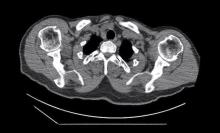

A 53-year-old male patient with cerebral palsy was admitted to a health center with contraction of his muscles. After his physical and other examinations were completed, a tumor believed to be a parathyroid adenoma was detected. His parathormone (494.6 pg/ml) and calcium (12.33 mg/dl) levels were very high. He was referred to the authors’ clinic when parathyroid scintigraphy showed that the adenoma was located in the mediastinum. The authors recommended robotic resection for mediastinal parathyroid adenoma. The resection was performed without any difficulty. No blood samples were taken intraoperatively. The pathological findings showed that the tumor was indeed a parathyroid adenoma. The postoperative course was uneventful, and the patient was discharged on the third postoperative day. Blood samples taken on postoperative day seven showed that the parathormone (51.7 pg/ml) levels were in the normal range and calcium (7.81 mg/dl) levels were in the low range. These blood levels are compatible with "Hungry Bone Syndrome.”